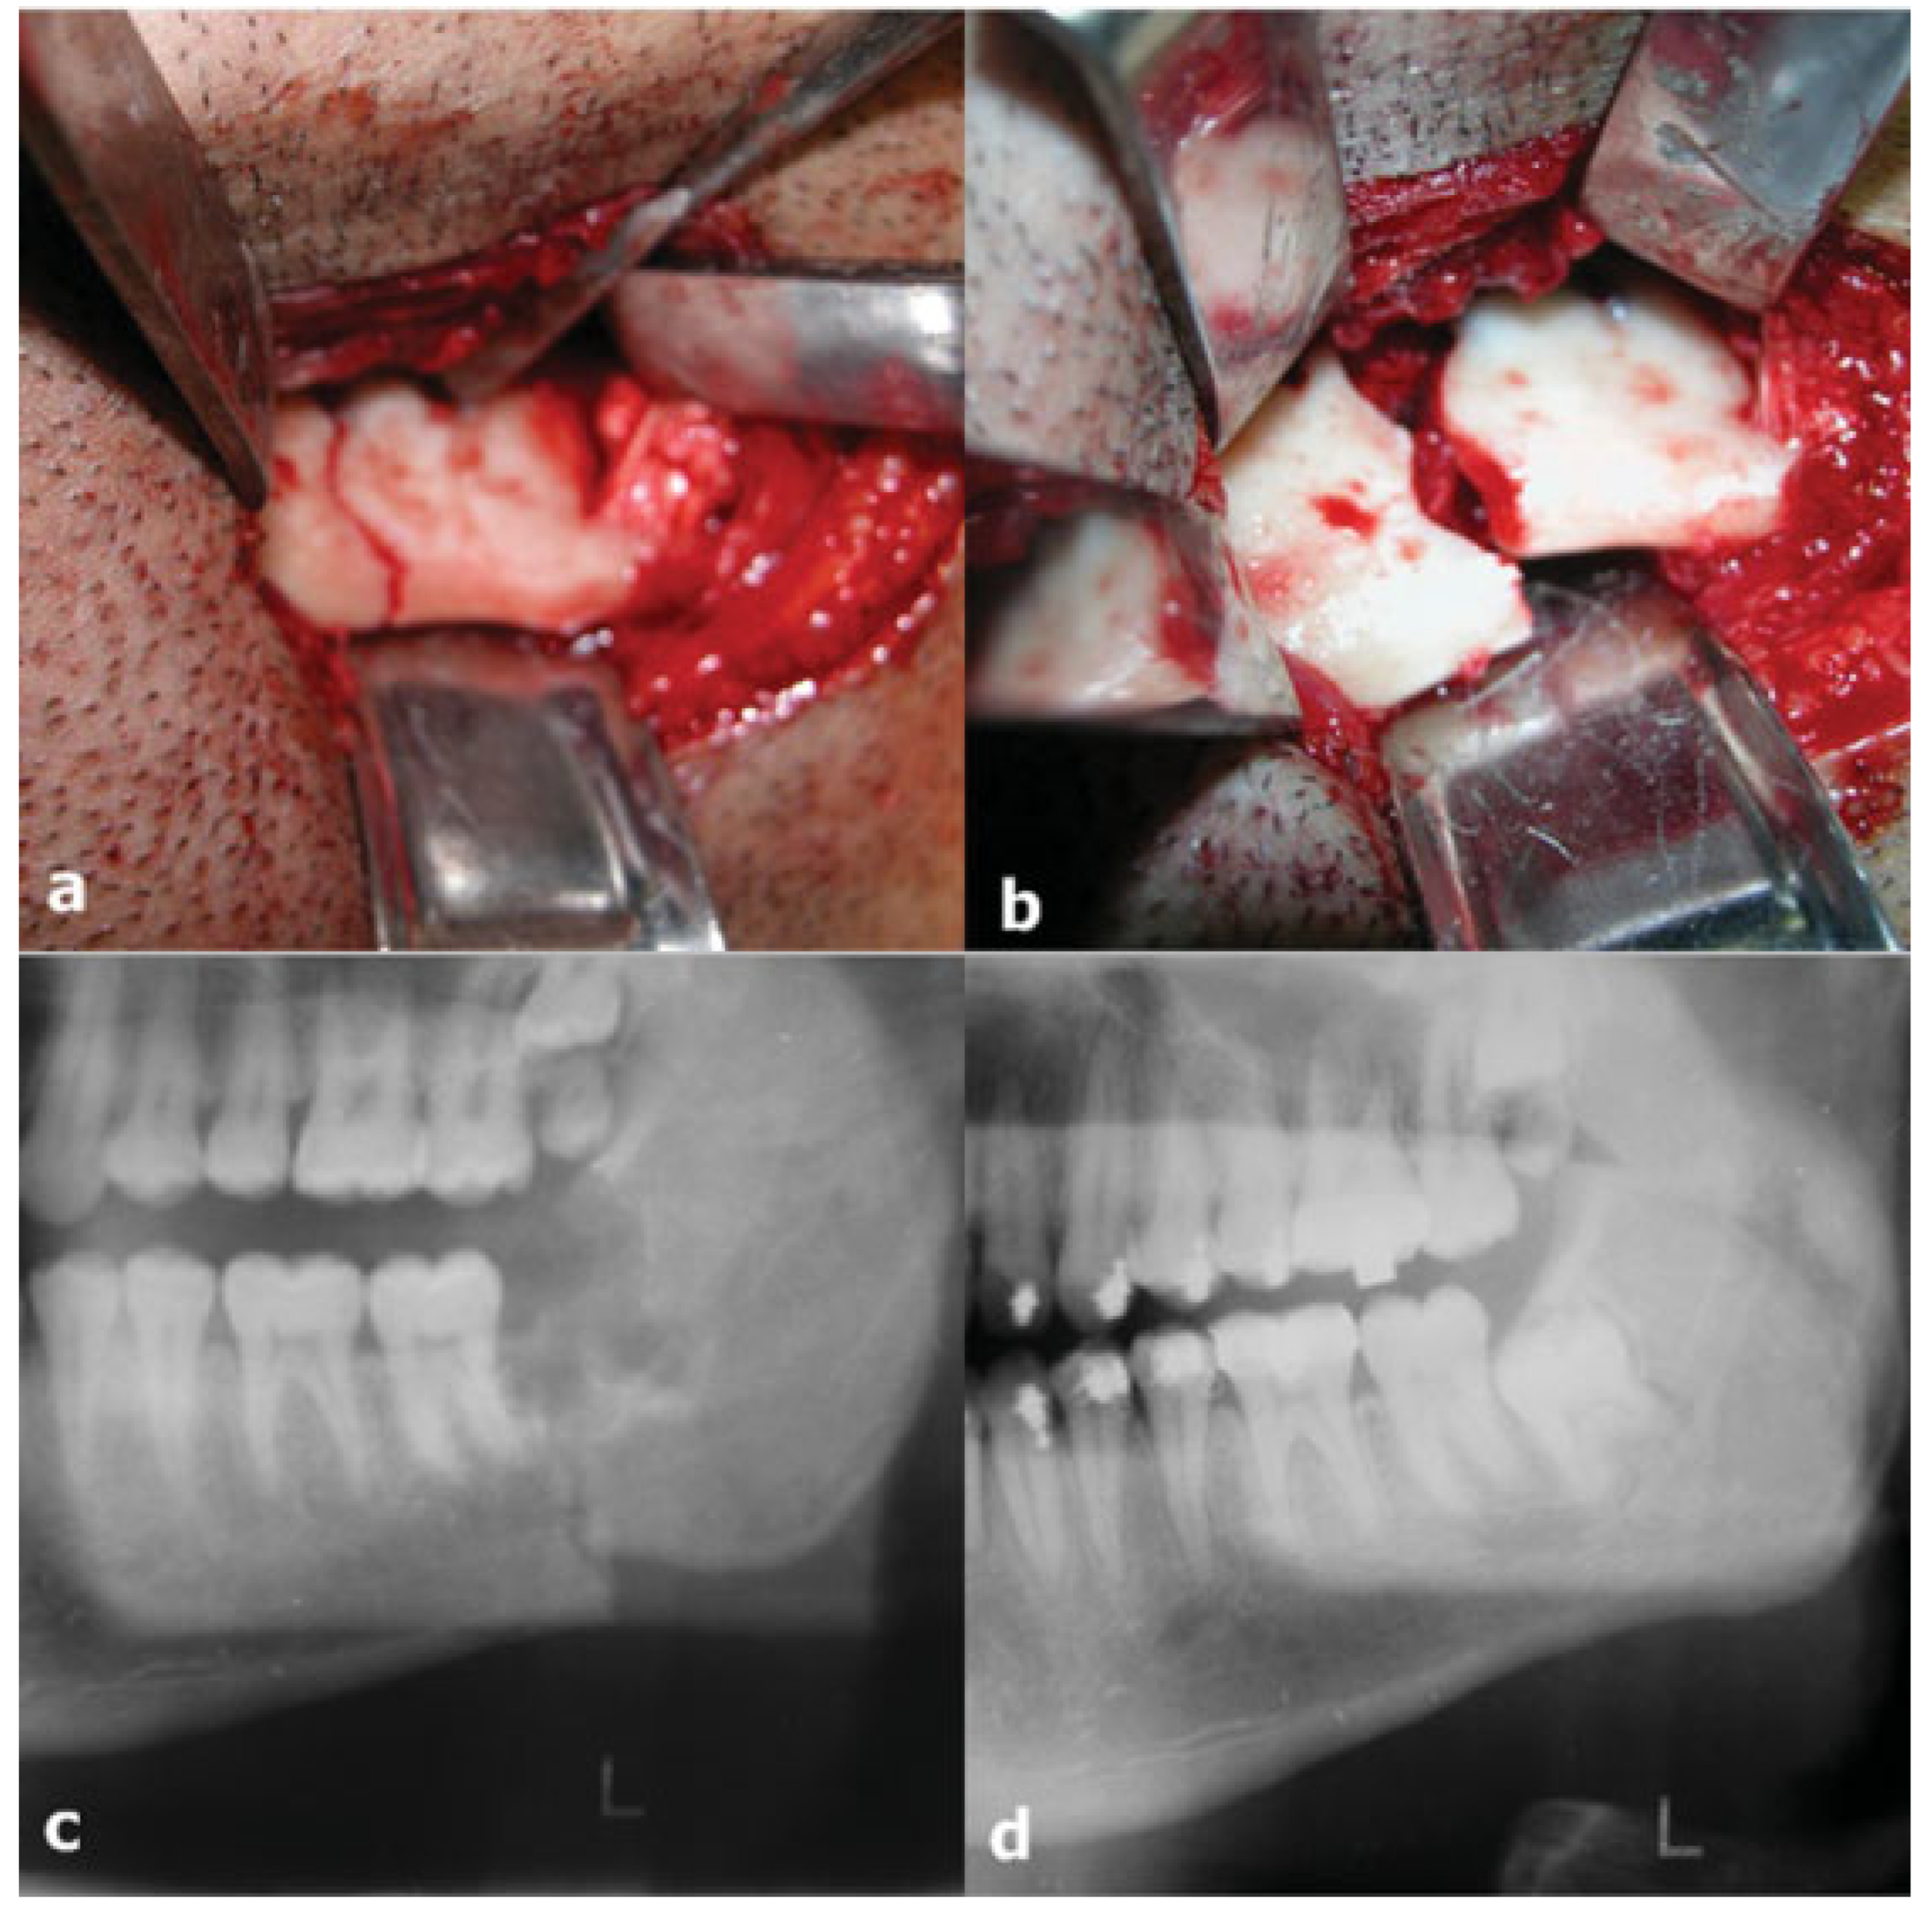

1.3. Case 3